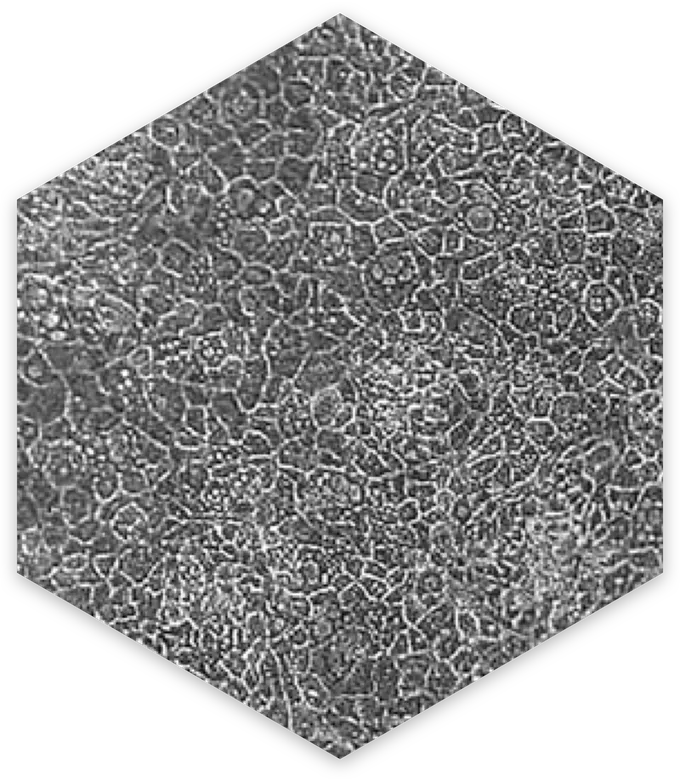

Def-HEP A1ATD cell morphology

The Def-HEP A1ATD cells are patient representative human hepatocytes. When thawed and plated Def-HEP A1ATD cells form a monolayer with typical hepatocyte cobblestone morphology.